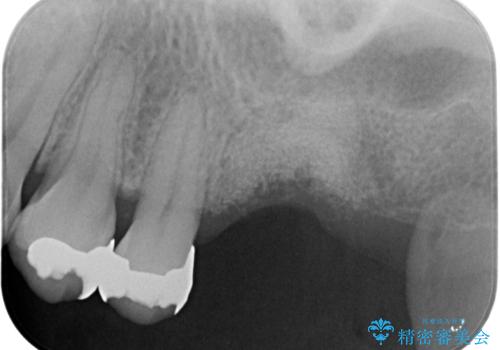

上顎奥歯のインプラント治療

- 奥歯を失い咬合機能の回復のためインプラント治療を希望され来院されました。

奥歯を2本失うと、他の歯の負担が増加し残っている歯の状態が悪くなるリスクがあります。

しっかりと咬合機能の回復できるインプラント治療を計画します。

- 88万円(インプラント×2・チタンカスタムアバットメント×2・ジルコニアクラウン×2・仮歯×2)費用は治療当時の料金となります